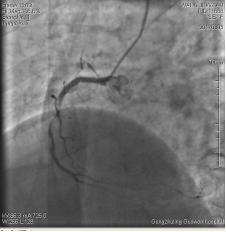

3月3日14時(shí)30分:經(jīng)右橈動(dòng)脈行冠脈造影見(jiàn):左主干未見(jiàn)明顯異常,TIMI血流3級(jí),前降支開(kāi)口正常,近中段20%狹窄,TIMI血流3級(jí);回旋支開(kāi)口正常,中遠(yuǎn)段75%狹窄,TIMI血流3級(jí)。右冠狀動(dòng)脈開(kāi)口正常,中段長(zhǎng)病變,最重99%狹窄, TIMI血流3級(jí)。

圖1 回旋支遠(yuǎn)段70%狹窄 圖2右冠脈中段99%狹窄